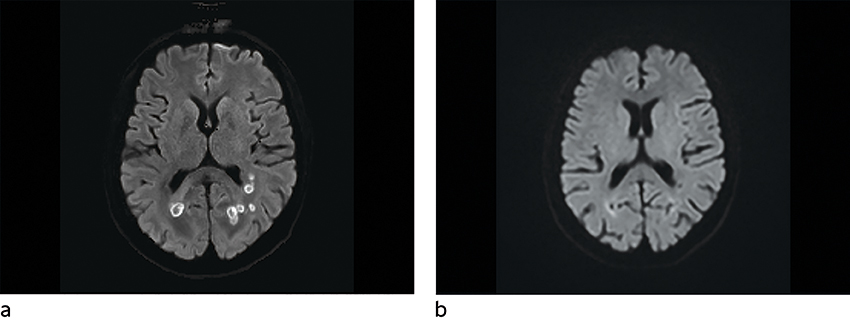

Påfølgende dag gikk man over til kombinasjonsbehandling med isavukonazol (200 mg × 3 første døgn, deretter 200 mg × 1) og liposomalt amfotericin B 5 mg/kg × 1 i totalt fire uker, med god toleranse. Deretter fikk hun monoterapi med isavukonazol 200 mg × 1 over tre måneder. Hodepinen forsvant raskt etter behandlingsstart, og etter få døgn var synsfeltutfallene borte. Det oppsto ingen bivirkninger av behandlingen. MR-undersøkelser, som ble utført annenhver uke de første to månedene, viste gradvis reduksjon av abscesser og ødem. Siste kontroll etter tre måneder viste kun minimale restforandringer.